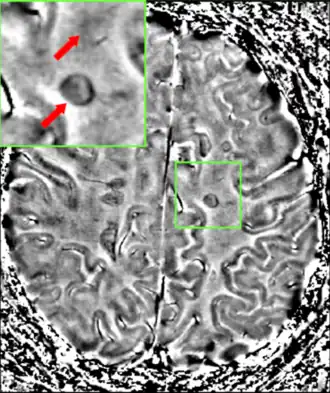

MRI

Magnetic resonance imaging (MRI) of the brain and spine may show areas of demyelination (lesions or plaques). Gadolinium can be administered intravenously as a contrast agent to highlight active plaques, and by elimination, demonstrate the existence of historical lesions not associated with symptoms at the moment of the evaluation.[94][95]

Central vein signs (CVSs) have been proposed as a good indicator of MS in comparison with other conditions causing white lesions.[96][97][98][99] One small study found fewer CVSs in older and hypertensive people.[100] Further research on CVS as a biomarker for MS is ongoing.[101]

In vivo vs postmortem lesion visibility in MRI scans

Only postmortem MRI allows visualization of sub-millimetric lesions in cortical layers and in the cerebellar cortex.[102]